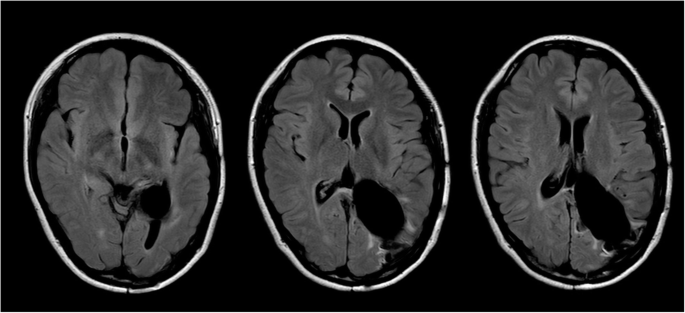

Our first impression derived from these findings was acute intracranial hemorrhage in the left ventricular trigone, although the cause of the hemorrhage was unclear. Her clinical status was so bad that urgent extraction of the hematoma was performed in order to save her life. A massive hematoma was removed and the enlarged left lateral ventricle was opened through the occipital pole cortex via a left occipitoparietal craniotomy. The hematoma consisted of one part that could be easily evacuated and another part, located mainly on the deep side, that was solid and bled easily. The surgery was terminated after confirming that a large amount of the hematoma had been debulked, leaving a portion in which hemostasis was difficult. Histological examinations of the solid part revealed a meningioma with massive hemorrhage within the tumor and many irregular vessels, including softened thin-walled vessels, closed vessels, etc., at the peripheral area of the tumor (Fig. 2). Closed arteries with organized reaction suggested a possibility of old hemorrhage. Spindle-shaped tumor cells were arranged in fascicular or storiform structures, and a few psammoma bodies were observed. Nuclear atypia or mitosis was rarely seen, and the Ki-67 proliferative index was less than 3 %. The tumor also extended to the choroid plexus, suggesting its derivation. The diagnosis of the 1st surgical specimen was fibrous meningioma, WHO grade 1. The intracranial hematoma was therefore thought to be due to intratumoral hemorrhage in a left lateral ventricular trigone meningioma. Postoperatively, the patient recovered well, but was diagnosed with right homonymous hemianopsia, right hemiparesis, and right abducens nerve palsy. Cerebral angiography was performed 5 days after the first operation and did not show any abnormality such as aneurysm, vascular malformation, or tumor satin. However, follow-up head CT demonstrated a residual tumor in the trigone of the left lateral ventricle (Fig. 3).

At 42 days after admission to our institution, 2nd surgery was performed to remove the residual tumor using the same approach as in the 1st surgery. The tumor was found to be relatively soft and well-demarcated. It arose from the choroid plexus, with arterial blood supplied from the medial and posterior lateral choroidal arteries, and was removed completely. Microscopic examinations of the 2nd surgical specimen yielded a diagnosis of fibroblastic meningioma with a Ki-67 proliferative index of l − 2 %. Abundant hemosiderin deposits, indicating prior hemorrhage, were visible within the tumor. The patient’s 2nd postoperative course was uneventful, and no residual intraventricular tumor was found on her follow-up imaging (Fig. 4). She was discharged from our hospital after the 30th post-2nd-surgery day. She was seen to be in a good state at the 15-month follow-up, demonstrating recovery from her right hemiparesis and right abducens nerve palsy, although her hemianopsia was not resolved.